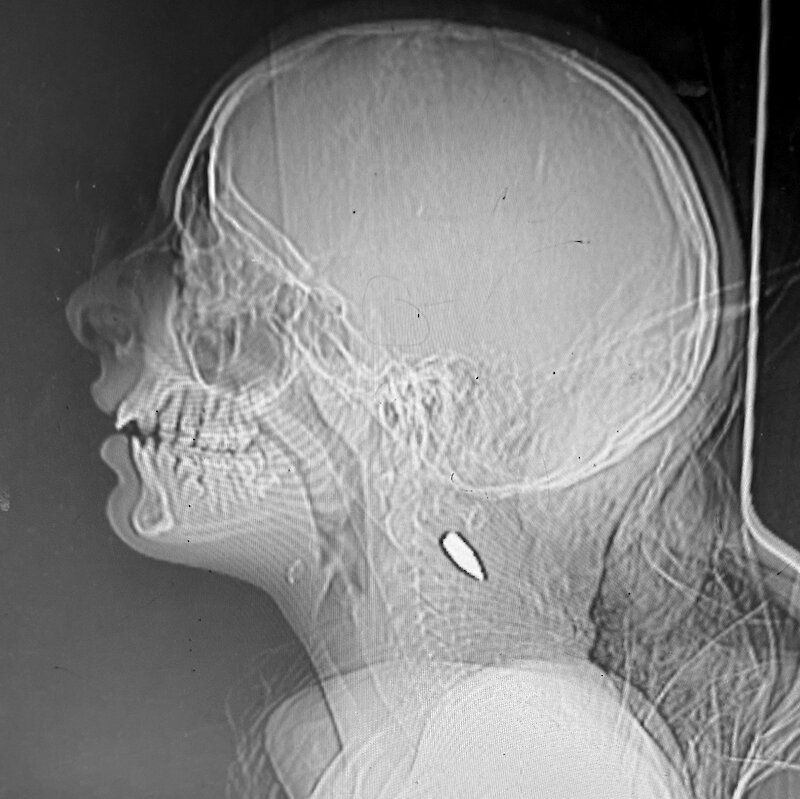

15 международных врач:инь, работавших в секторе Газа, сообщили нидерландской газете de Volkskrant, что видели как минимум 114 детей в возрасте пятнадцати лет и младше с одиночными пулевыми ранениями в голову и грудь. Это может быть признаком того, что израильские военные преднамеренно отстреливают детей в секторе Газа.

Одиночные пулевые ранения в голову и грудь.

По словам врач:инь и очевидцев обстрелов, большинство детей были застрелены снайпер:ками ЦАХАЛ или беспилотниками. Бывший командующий сухопутными войсками Нидерландов Март де Кройф в комментарии de Volkskrant утверждает, что вероятность случайных попаданий практически равна нулю, учитывая более ста задокументированных врач:инями случаев.